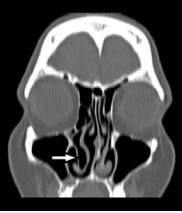

The coronal CT image of the right inferior concha bullosa.

Figure 2:The coronal CT image of the right inferior concha bullosa.